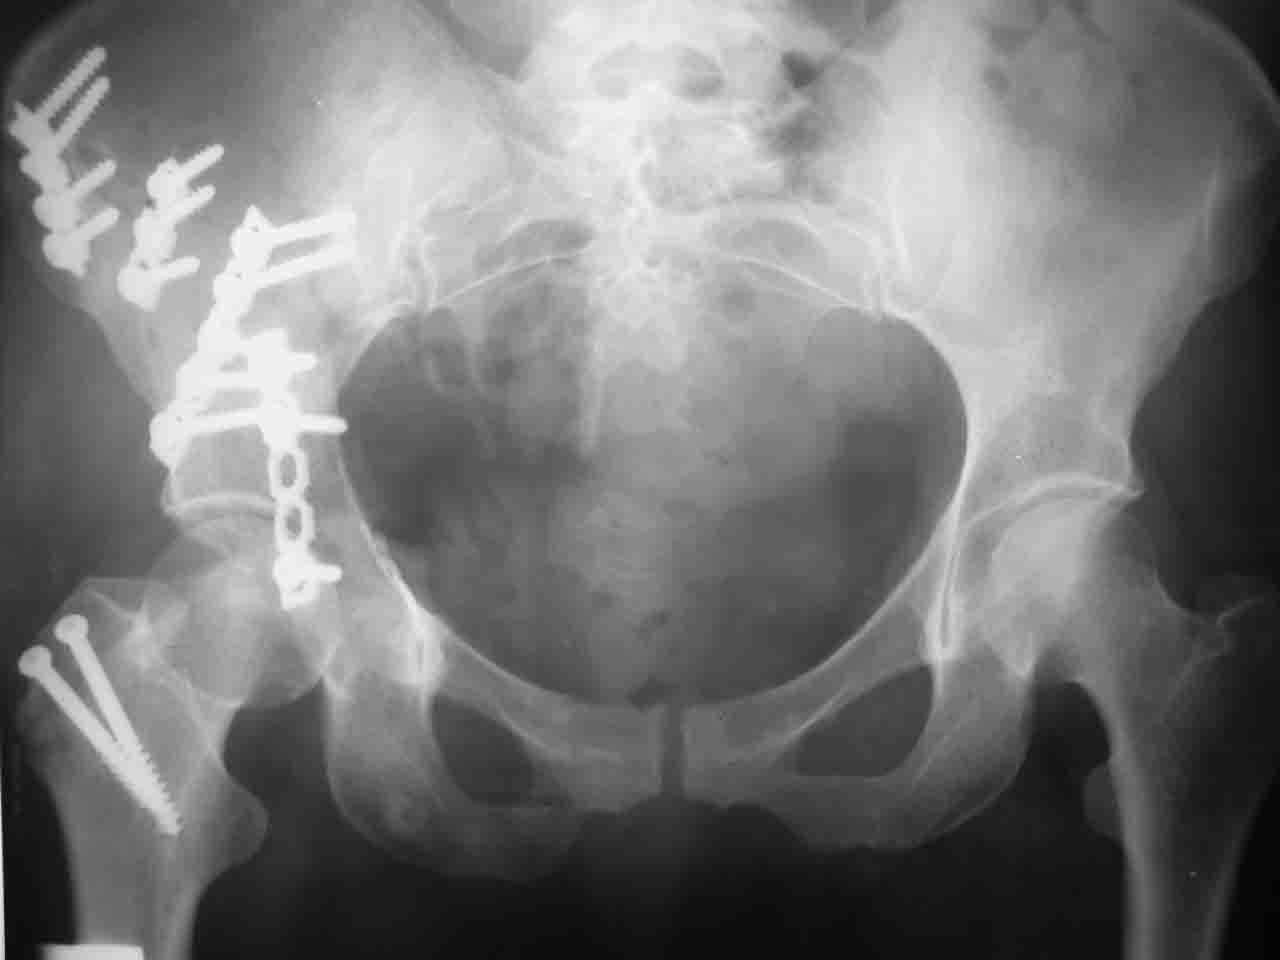

Вопрос доступа к вертлужной впадине при остеосинтезе задача не простая. Конечно, у Летурнеля и Тайла всё давно описано, нам остается только брать на вооружение. Но сами понимаете, что не бывает двух одинаковых ситуаций, поэтому в каждом случае вопрос решается сугубо индивидуально. Наша главная цель - восстановить анатомию с нанесением минимальной дополнительной травмы тазобедреннному суставу, думаю с этим никто не поспорит. Расширенный илиофеморальный доступ уж слишком травматичен (как сказал один коллега "таз лежит отдельно, больной отдельно").Стоит ли делать из пациента анатомический препарат для того чтобы легче ориентироваться. Да и нужно ли собирать всю "мозаику"? Мы применяли при таких операциях своеобразную операционную хитрость - сначала устраняли грубое смещение крыла под гребнем с фиксацией так называемой "плавающей" пластиной (временно фиксированной на двух винтах)- доступ или продлевали боковой, или делали небольшой дополнительный разрез над гребнем. Это позволяло устранить грубое смещение и захождение отломков тела повздошной кости, что значительно облегчало репозицию и остеосинтез впадины над сводом. Основное внимание конечно же уделяли нагружаемому задне-верхнему отделу. Сообщите ваш адрес, пришлю схемы и рентгенограммы.

С уважением, Алексей.